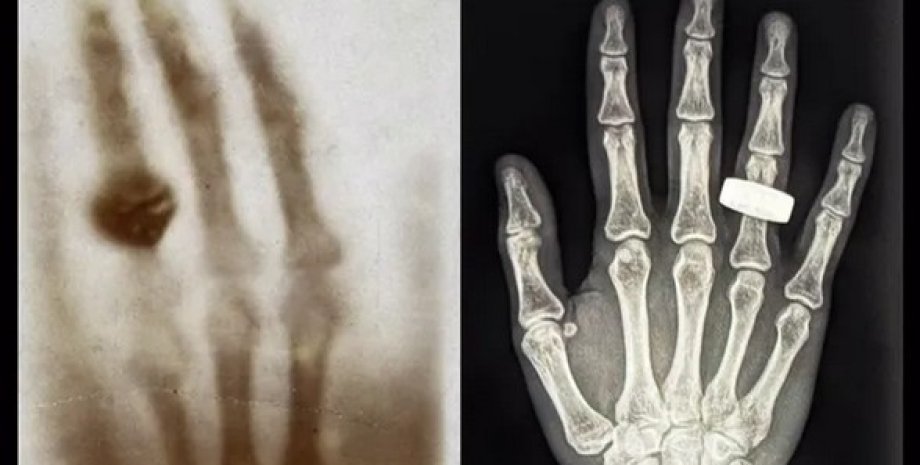

1895 року фізик Вільгельм Рентген уперше відкрив рентгенівські промені та зрозумів, що вони можуть бути корисними для медицини. У підсумку вчений зробив перший в історії рентгенівський знімок людського тіла. Це було зображення руки його дружини з обручкою. Через 130 років учасники місії Fram2 відтворили цю рентгенівську фотографію, але вже в космосі.

За цей час космічні туристи провели 22 наукові експерименти, зокрема вони спостерігали за полюсами нашої планети, вирощували гриби і зробили перший в історії рентгенівський знімок людського тіла на орбіті, який показала компанія SpaceX.

Після того, як екіпаж місії Fram2 зробив рентгенівське зображення кисті руки, демонстрація цієї технології була продовжена серією інших діагностичних знімків, які включали передпліччя, таз, живіт і груди людини. Приватні астронавти також зробили знімки електроніки, щоб перевірити як можна використовувати рентгенівські промені для діагностики роботи приладів космічного корабля.